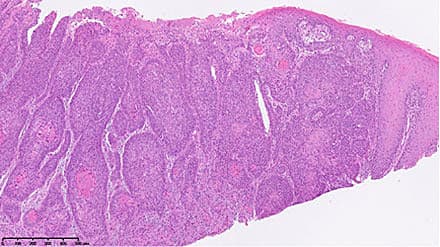

Planocellulær analcancer (her omtalt som analcancer) opstår i analkanalen (området mellem den palpable

del af musculus puborectalis og begyndelsen af den

behårede hud) eller i den anale margin (op til 5 cm

fra analåbningen). Aldersstandardiseret incidens pr. 100.000 personer pr. år er hos kvinder øget fra 0,66 i perioden 1978-1982 til 1,48 i perioden 2004-2008 og hos mænd fra 0,37 til 0,78 i samme perioder [1, 2].

Risikofaktorer er human papillom-virus (HPV)-infektion, immunsupression, analt samleje, hiv-infektion, høj alder, tidligere cervixcancer og rygning. 80-90% af patienterne med analcancer er HPV-positive [3, 4]. Symptomerne (blødning, kløe, smerter og sekretion eller følelse af udfyldning ved analåbningen) er typisk vage [5]. Sygdommen forveksles ofte med hæmorroider.